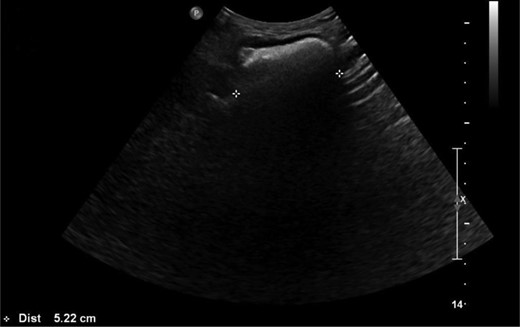

CT scan of the pelvis did not identify a cause for the swelling (Fig. 1). Due to the positional nature of the swelling, a gluteal ultrasound was organized, which revealed a large colonic sciatic hernia (Fig. 2). As the patient had minimal symptoms and was not keen for surgical intervention, a plan for conservative management was agreed and the patient was discharged from clinic.

Ultrasound image demonstrating the sciatic hernia. (Reported as ‘US Hip Rt: Confirms reducible herniation of colon in the right sciatic region into the buttock.’)